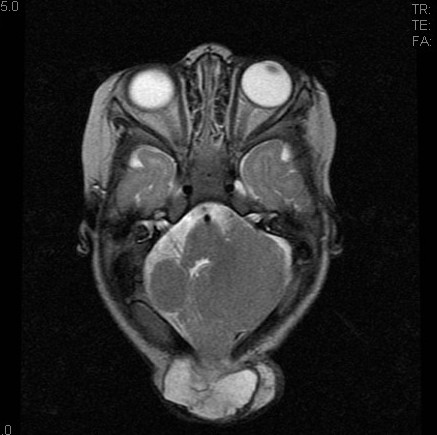

3型もあるぜ! キアリ奇形3型 ☑後頭部に大きな脳隆人小脳・脳幹が嵌入 ☑非常に稀で随伴奇形も多く、予後は他の方と比べると不良 ☑4、5型もあり、なんなら0、1.5、3.5とかもある(ただし一部は廃止されてたりもする) Radiopedia rID:5781, rID:17478 #Rdiag

3型もあるぜ!

キアリ奇形3型

☑後頭部に大きな脳隆人小脳・脳幹が嵌入

☑非常に稀で随伴奇形も多く、予後は他の方と比べると不良

☑4、5型もあり、なんなら0、1.5、3.5とかもある(ただし一部は廃止されてたりもする)

Radiopedia rID:5781, rID:17478